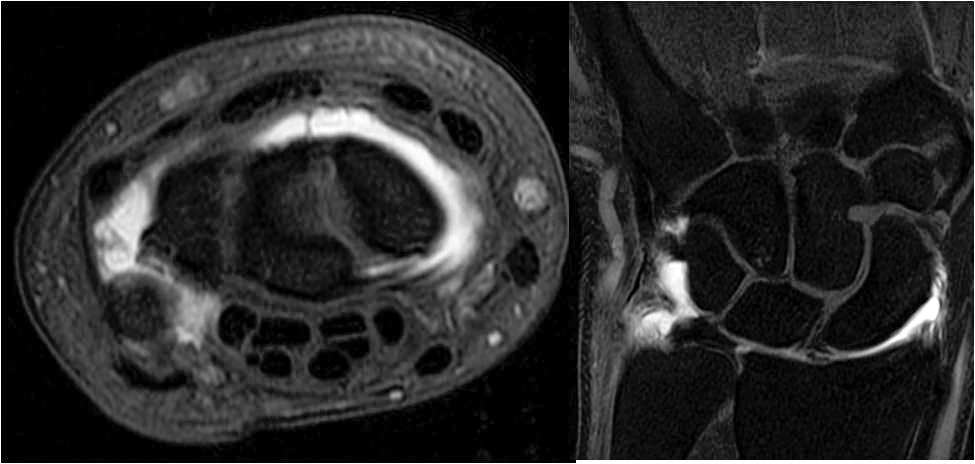

• Musculoskeletal Radiology →

Musculoskeletal Radiology

The mission of the Musculoskeletal Radiology Fellowship Program at UMass Chan Medical School is to provide fellows with high-level, state-of-the-art training in musculoskeletal radiology, and to produce skilled and competent musculoskeletal radiologists who will succeed in both academic and private practices.